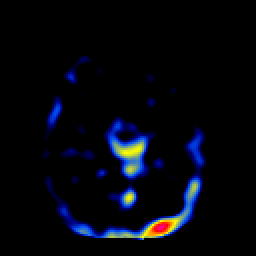

SPECT TL Study #2 -- Slice #36

[Home][Help][Clinical][Tour 1][Tour 2][Tour 3] Slice 36